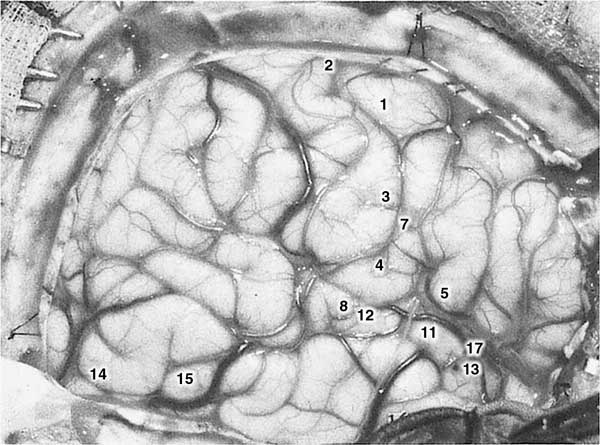

11 – «Я что-то слышала, но не знаю, что это было». 11 – (повторный, без предупреждения): «Да, сэр, я думаю, я слышала, как мать зовет своего малыша. Казалось, что это происходило много лет назад». Когда пациентку попросили объяснить, она сказала: «Это происходило по соседству со мной». Затем она добавила, что она сама «находилась где-то очень близко, чтобы расслышать». 12 – «Да. Я слышала голоса где-то внизу у реки – мужской и женский голоса звали… Я думаю, я видела реку». 15 – «Просто крошечная вспышка чувства того, что это мне знакомо и чувство того, что я знаю все, что должно произойти в ближайшем будущем». 17с – (Игла, полностью изолированная, за исключением кончика, вводилась в верхнюю поверхность височной доли в глубине Сильвиевой борозды, после чего пускался ток.) «О! У меня были те же самые, очень знакомые воспоминания, где-то в офисе. Я видела офисные столы. Я была там, и кто-то звал меня, мужчина, прислонившийся к столу, с карандашом в руке». Я предупредил пациентку, что собираюсь стимулировать ее, но не делал этого. «Ничего». 18а – (Стимуляция без предварительного предупреждения.) «У меня было мало воспоминаний – сцена в пьесе: они разговаривали, и я могла это видеть – я просто видела это в моих воспоминаниях». Рис. 3. Случай М. М. ![]() Пациент лежит на операционном столе. Местный анальгетик введен в череп, а места разрезов отмечены линиями на коже. См. Библиографию.19 Эта фотография помещена здесь с целью напомнить читателю о том, что хотя хирург и пациент во время операции скрыты друг от друга стерильным полотном, они все же находятся рядом. Симпатия и взаимопонимание помогли этим пациентам свободно обсуждать с доктором их мысли и чувства во время электрической стимуляции мозга и удаления зарубцевавшихся извилин. Хотя мозг сам не чувствителен и не может быть источником боли, операции иногда бывают долгими, опасными и чрезвычайно утомительными. Интеллектуальный интерес и точные ответы этих неизменно любезных пациентов внесли большой вклад в это исследование физиологии мышления и разума. Рис 4. Случай М. М. ![]() Правое полушарие вскрыто. Цифры обозначают, в каких точках стимуляции отмечались реакции на электроды хирурга. Рис. 5. Случай М. М. ![]() Диаграмма оперативного поля и точки положительных реакций. Прерывистая линия указывает на размеры удаления височной доли в процессе операции по поводу фокальной эпилепсии. Штриховкой отмечены поверхности склероза и атрофии, возникшей из-за, по всей вероятности, давления на мозг в момент родов. Рис. 6. Активация записей потока сознания в мозге и другие результаты стимуляции. ![]() 1 От интерпретативной коры – дистанционная активация потока сознания 2 От соматической моторной коры – дистанционная активация движений правой руки 3 От сомато-сенсорной коры – дистанционная активация чувствительности правой руки 4 В речевой коре – расстройства и афазия 5 От сенсорной зрительной коры – дистанционная активация чувствительности к свету 6 Сильвиева борозда 7 Височная доля 8 Спинной мозг Для иллюстрации результатов стимуляции электродом коры мозга в ее моторной, сенсорной и той, что можно назвать психической, зонах, проводившейся в целях извлечения из памяти прошлого опыта, показаны очертания левого полушария мозга человека, под ними видны стволовая часть головного мозга и спинной мозг. Усеянные точками участки вокруг каждого кончика стимулирующего электрода (однополярного) предположительно являются областями расстройства, нарушения, в которых местные корковые действия, связанные с разработкой программы, блокируются интервенцией электричества. Вдобавок к этому вмешательству была отмечена положительная реакция от каждого из этих электродов, за исключением одного, применявшегося в области локализации речевой функции. Стимуляция речевой коры вызывает только интервенционную афазию. С другой стороны, положительные реакции вызываются нормальным проведением аксоном импульса от клеток, расположенных рядом с электродом, к отдаленным, но функционально родственным областям серого вещества. Таким образом, активная ответная реакция является результатом физиологической активации того отдаленного участка серого вещества. В случае стимуляции интерпретативной коры происходит активация последовательной записи состояния сознания, имевшего место в прошлом. Если стимулируется моторная кора, то «мишенью» для активации служит серое вещество нижнего отдела стволовой части головного мозга или спинной мозг. Когда стимуляции подвергаются сенсорные зоны коры, мишенью для активации становятся высшие отделы ствола мозга. Моему удивлению не было предела: каждый раз мой электрод стимулировал подобные ответные реакции. Как это работало? Несомненно, имеется какая-то связь с мышлением! Я назвал такие реакции эмпирическими и надеялся получить новые подтверждения своих догадок. Между тем в течение всего начального периода эксперимента мы были всецело заняты картированием сенсорной и моторной коры, а также речевой зоны коры мозга человека [9]. 29, 30 |